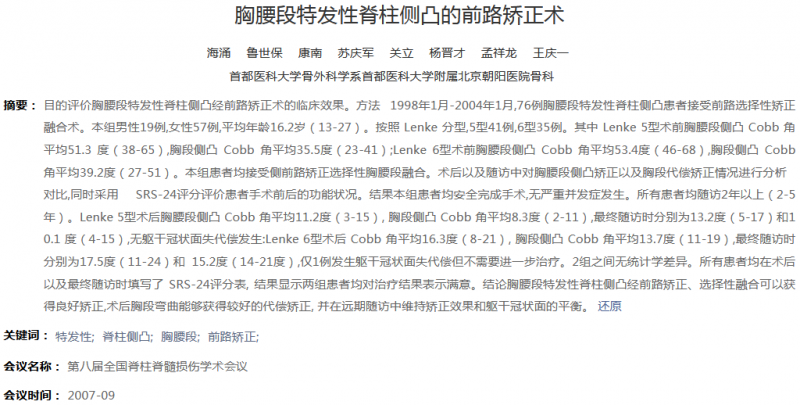

图4.北京朝阳医院骨科既往相关研究

4. 海涌, 鲁世保, 康南, 苏庆军, 关立, 杨晋才, 孟祥龙, 王庆一 胸腰段特发性脊柱侧凸的前路矫正术. In: 第八届全国脊柱脊髓损伤学术会议.